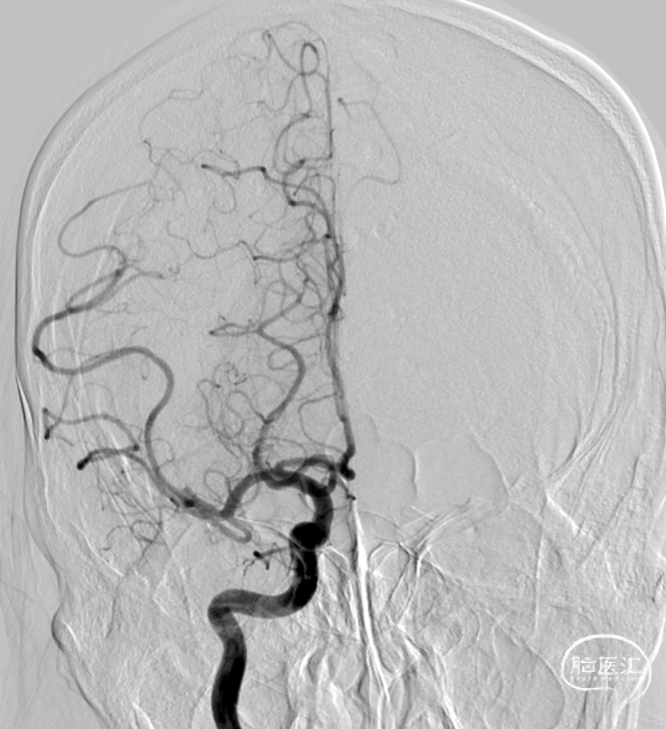

最终造影结果mTICI 2b

术后复查血管通畅,少许梗塞